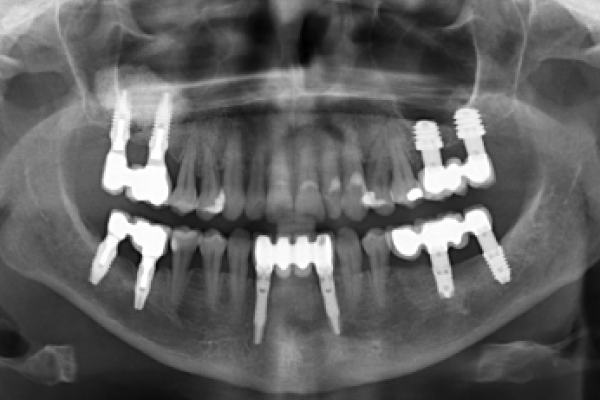

Técnica de All-on-4 como opción terapéutica en la rehabilitación mandibular completa: complicaciones técnicas, biológicas e índice de satisfacción de los pacientes

Nuevas técnicas de planificación y tratamiento para la rehabilitación maxilar con implantes cigomáticos. A propósito de un caso

Reconstrucción maxilar con un implante subperióstico en un caso de atrofia severa. De la planificación a la rehabilitación siguiendo un protocolo totalmente digital. A propósito de un caso clínico y revisión bibliográfica

Maxillary reconstruction with a subperiosteal implant in a case of severe atrophy. From planning to rehabilitation following a fully digital protocol. About a clinical case and bibliographic review

Rehabilitación inmediata con doble lateralización del nervio dentario inferior. A proposito de un caso clínico